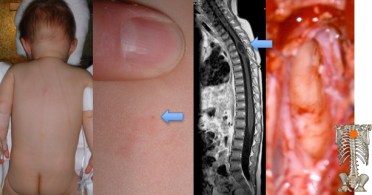

on trouve une lésion cutanée angiomateuse avec une fossette centrée par un ou plusieurs poils (A). l’IRM (B) montre un trajet sous-cutané qui pénètre jusqu’au rachis et se continue souvent en intra-dural. le trajet peut conduire à un kyste dermoïde correspondant à l’accumulation de squames d’épiderme (C), qui se situe dans les espaces arachnoïdiens ou au sein même de la moelle (graphique ci-dessus).